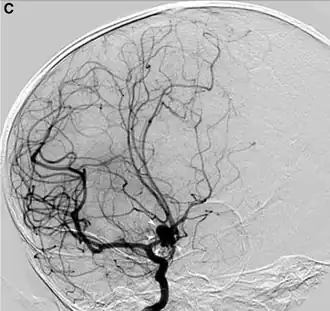

O exame padrão ouro para detecção de aneurisma cerebral não é a tomografia ou a ressonância magnética, e sim o cateterismo cerebral de 4 vasos (angiografia digital).

Um aneurisma cerebral é uma patologia provocada pela dilatação segmentar, em formato variável, de um vaso na massa encefálica (encéfalo), geralmente arterial ou, menos frequentemente, venoso, como por exemplo, o raro aneurisma da veia de Galeno.

Os aneurismas do encéfalo humano mais frequentes são conhecidos como aneurismas cerebrais congênitos e são mais encontrados na face inferior do encéfalo, na rede circulatória dos grandes vasos conhecida como polígono de Willis.